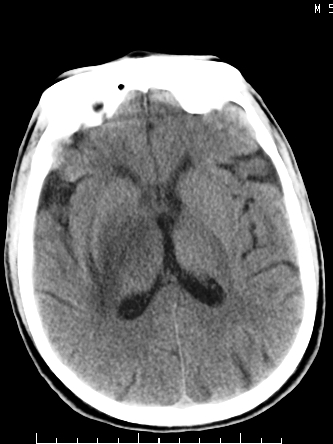

m/50,头昏头痛1月,近3天感觉左半肢体活动不利,自述半年前呈患肺tb,腰穿脑脊液未见特殊改变。现做头颅ct请大家会诊。

首先考虑肿瘤性病变,星形细胞瘤可能性大,不排外转移瘤。建议mri。

结核性脑膜炎,结核瘤,梗塞灶三症并存,提示颅内结核感染可能性大。

脑干占位,考虑转移瘤可能性大,不除外胶质瘤.

请大家结合临床表现看一下 左侧肢体的症状是脑干 还是其他的问题 另外结核感染脑脊液应该有问题 所以应该考虑肿瘤性病变

可考虑结核,患者水肿范围大,囊性病灶边缘密度较高,不考虑胶质母细胞瘤